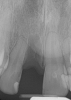

Fig 25. Postoperative periapical radiograph at 2 weeks.

Figure 25

Fig 28. Postoperative radiograph at 16 weeks.

Figure 28